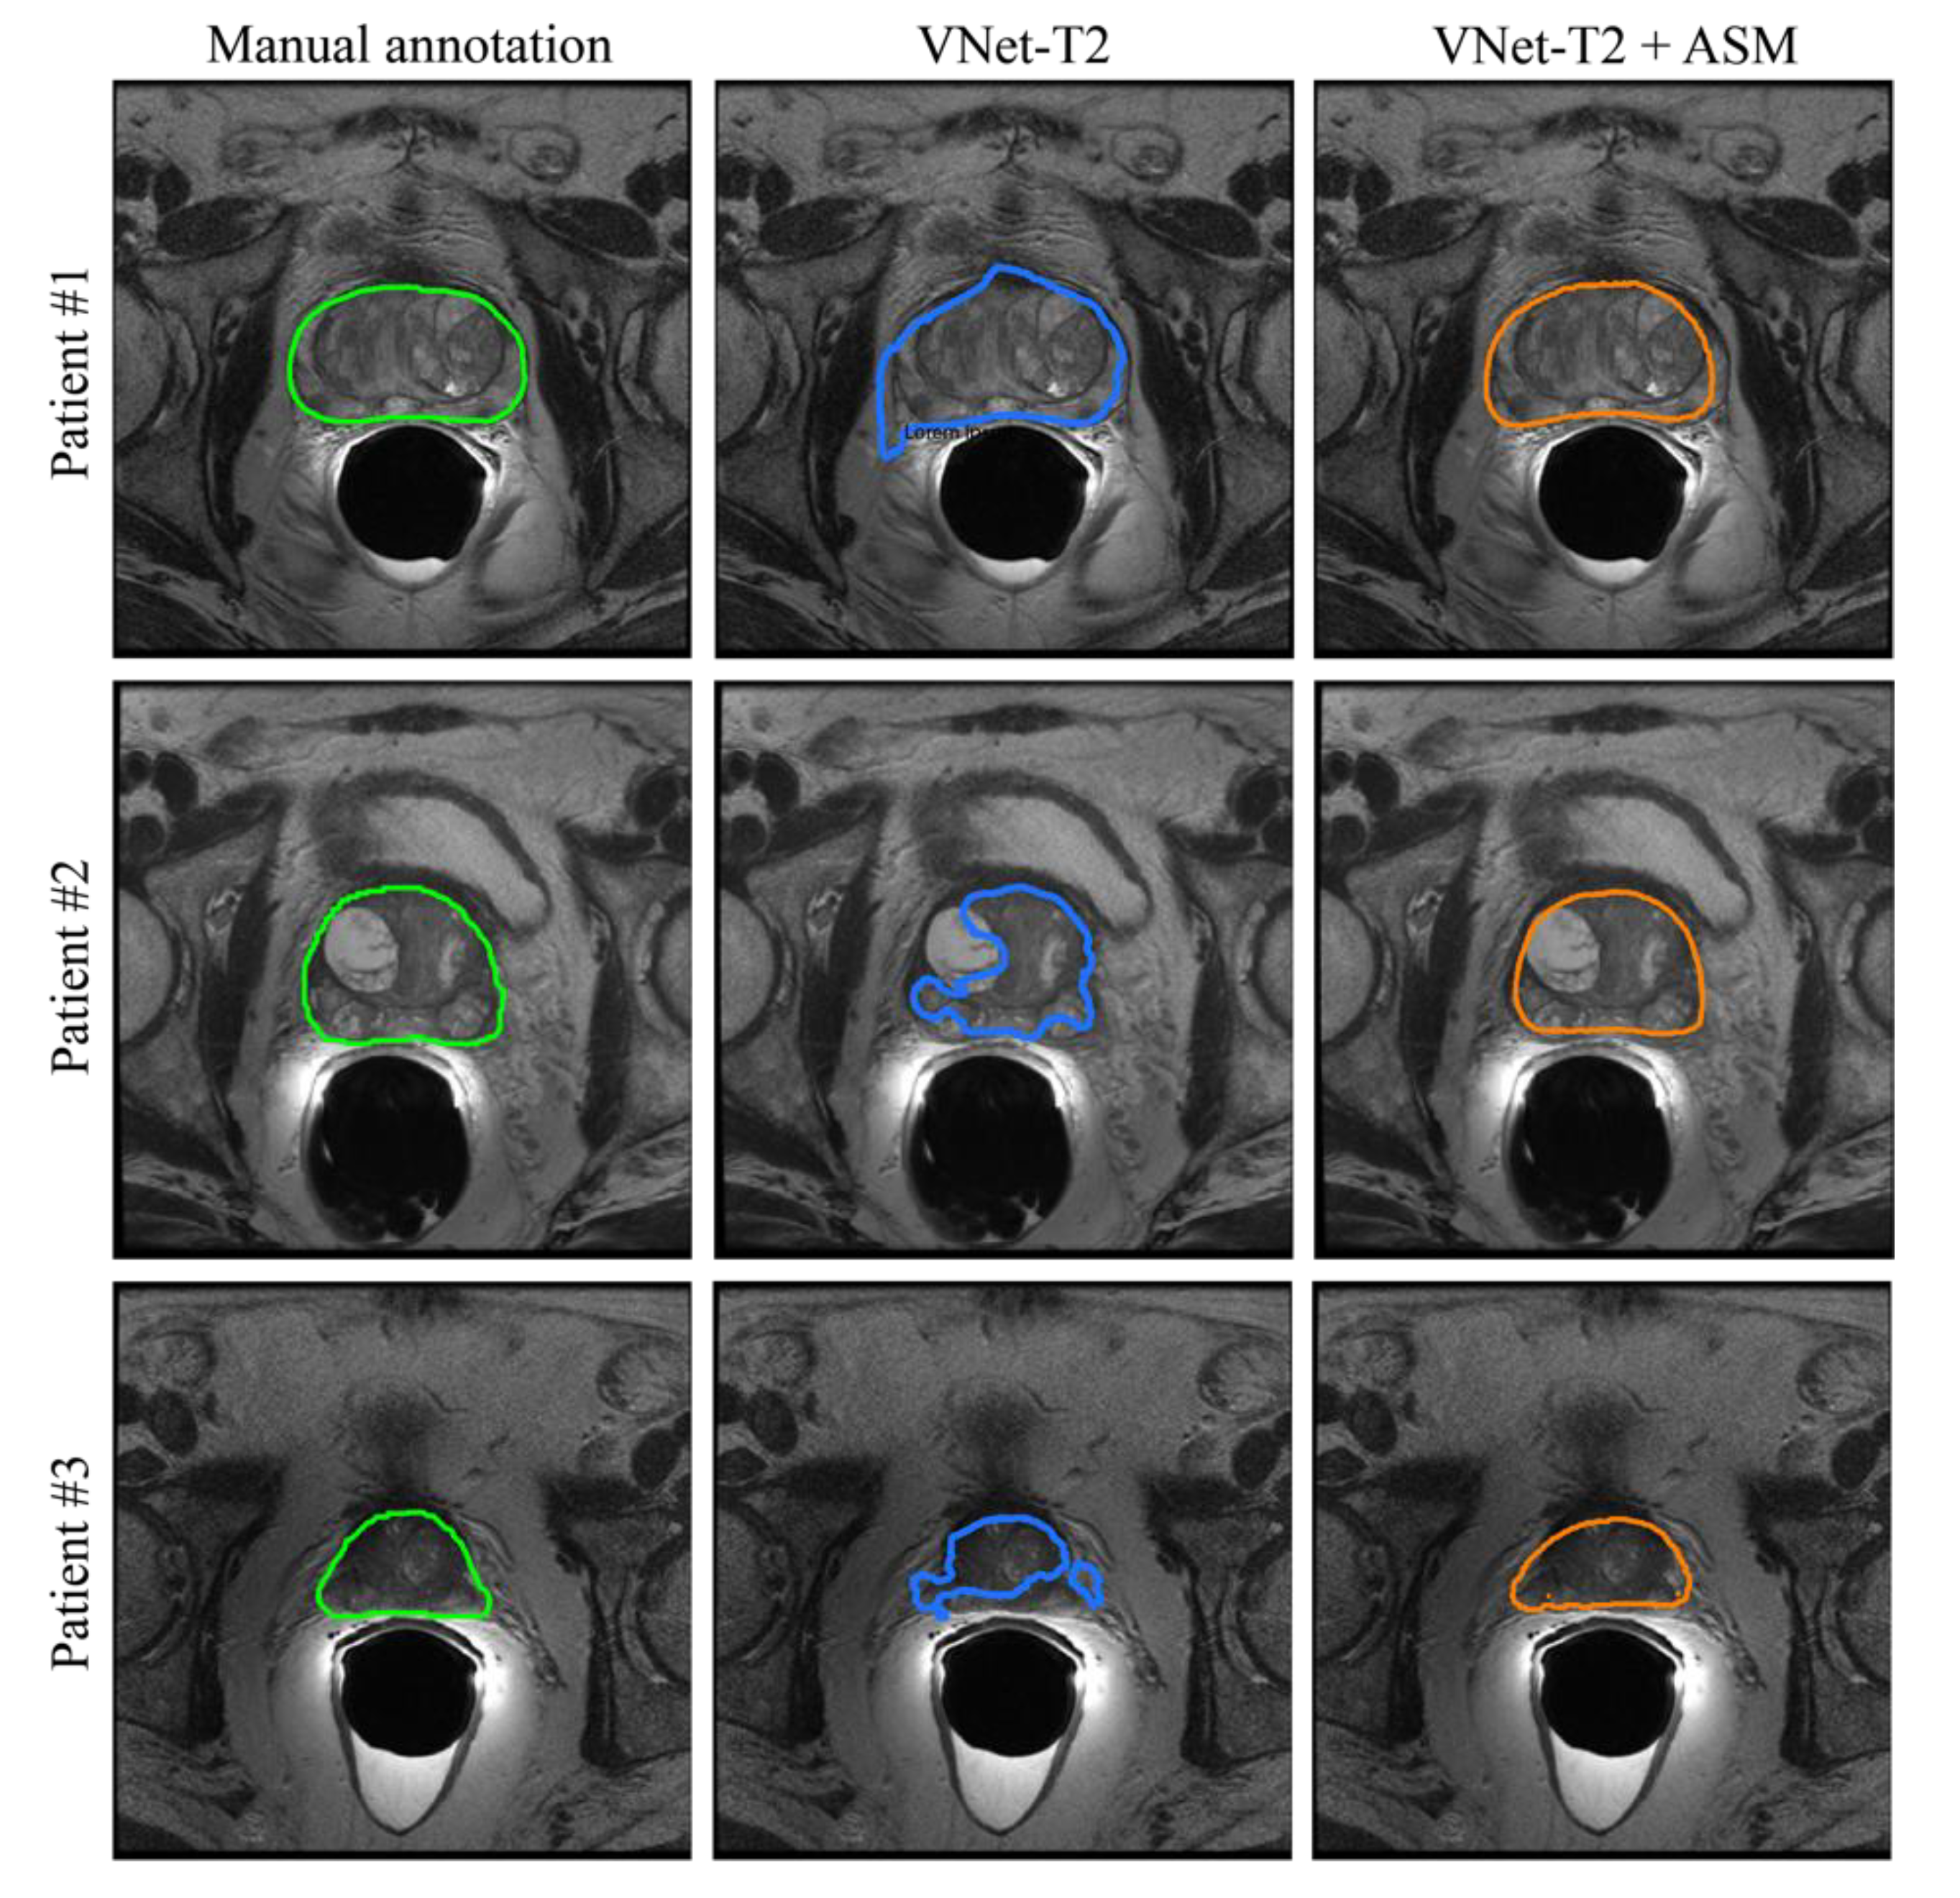

3. Results

3.1. Ablation Study

3.2. Inter-Observer Variability